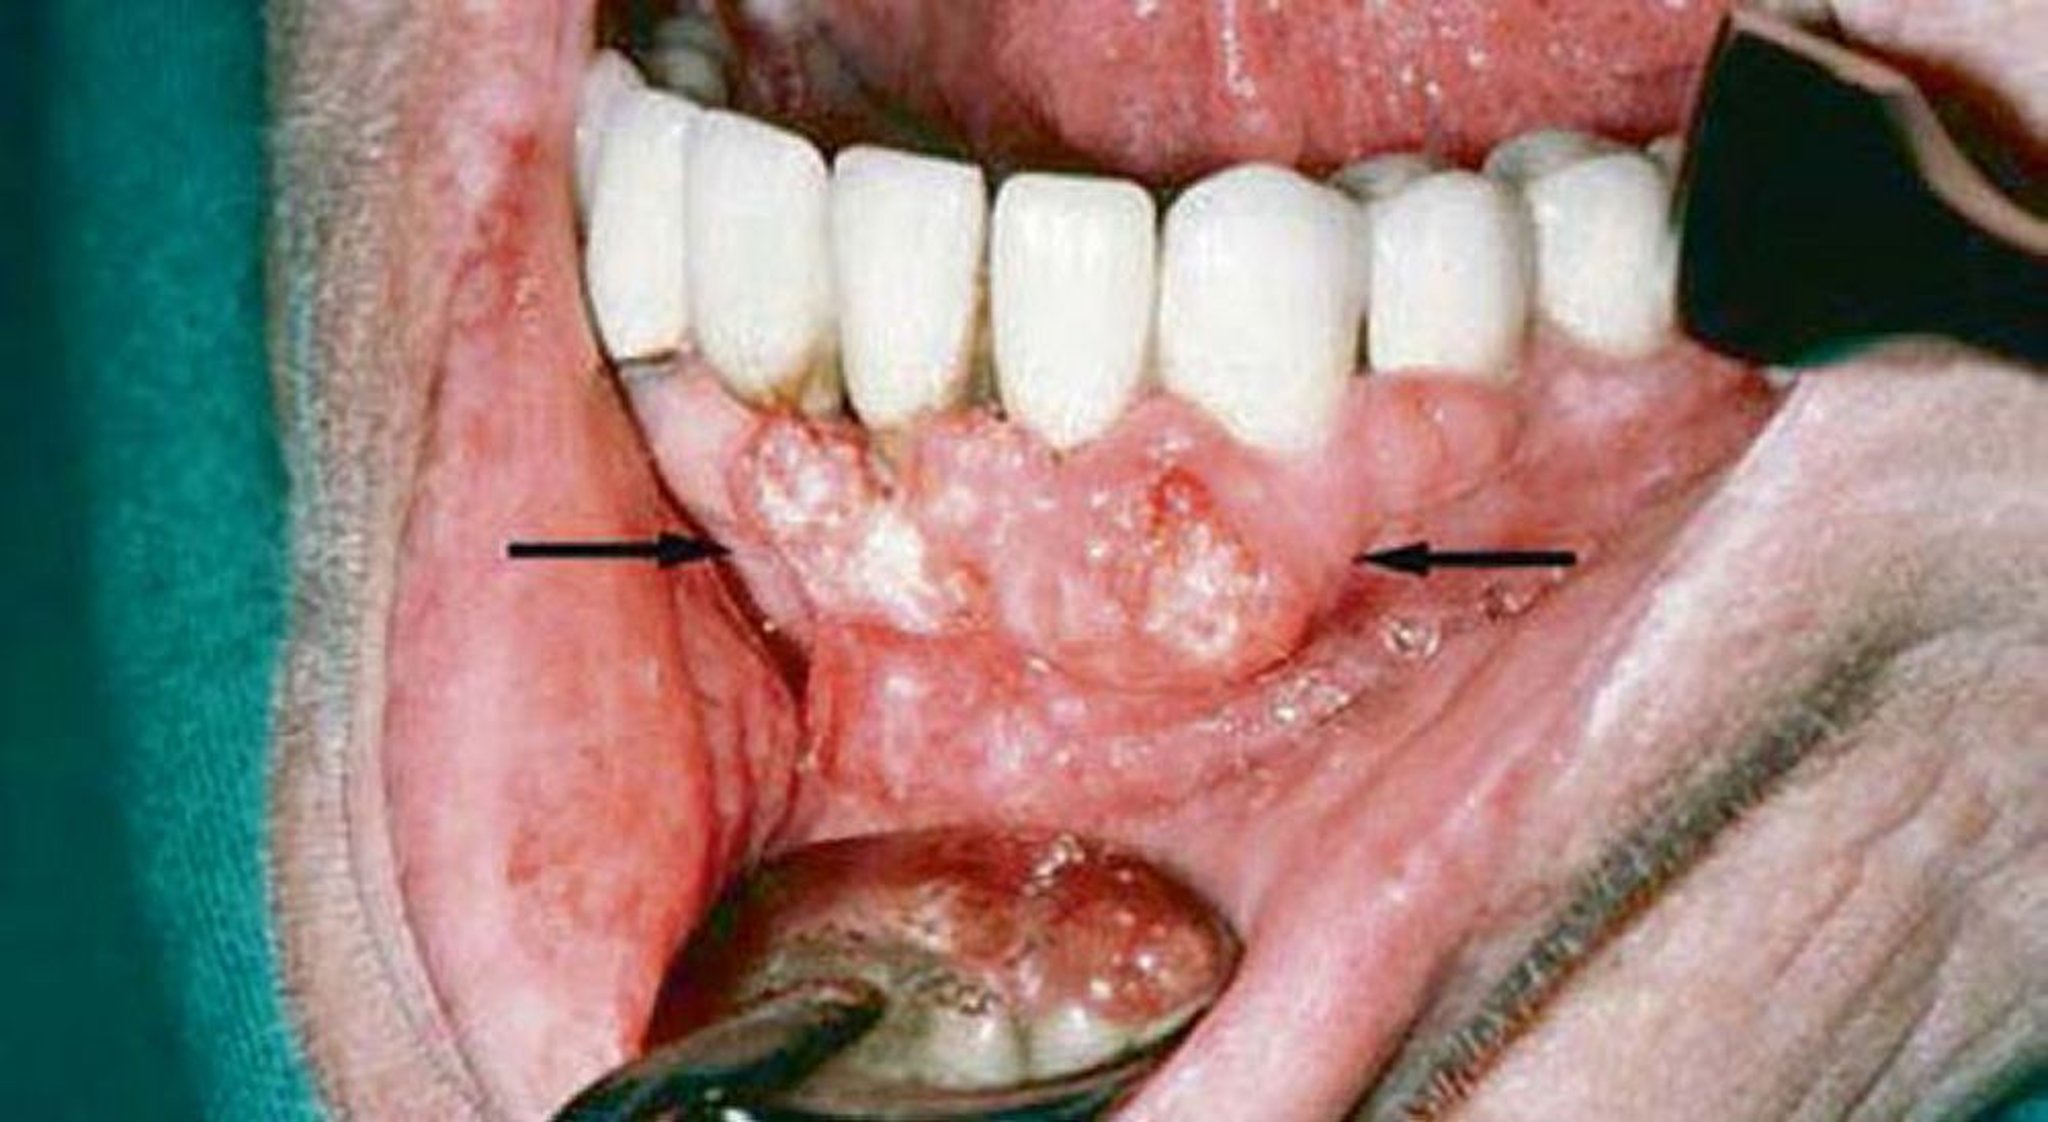

扁平上皮癌(歯肉病変)

この患者の歯肉の診察により,扁平上皮癌の所見が認められた。画像検査で下顎骨の浸潤が認められた。